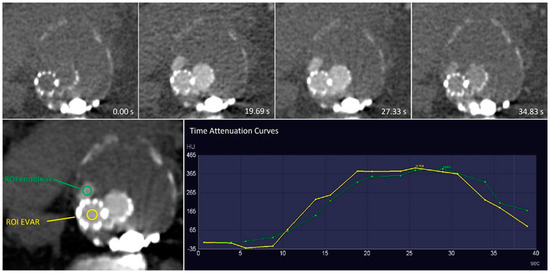

4.1. Time Attenuation Curves

| Patient No. | Endoleak | Branch | Peak Stent (HU) | Peak Endoleak | Peak Endoleak/ Stent (%) | Time Peak Stent (s) | Time Peak Endoleak (s) |

|---|---|---|---|---|---|---|---|

| 1 | 2× type II | AMI | 348.8 | 332.4 | 95.3 | 20.6 | 28.9 |

| L1 | 348.8 | 333.6 | 95.6 | 20.6 | 28.6 | ||

| 2 | 1× type II | L1 | 370.9 | 304.1 | 82 | 28.5 | 33.3 |

| 3 | 1× type IIIb | 459.9 | 425.8 | 92.6 | 25.6 | 28.9 | |

| 4 | 1× type II | L1 | 401.2 | 252.1 | 62.8 | 23.6 | 33.4 |

| 5 | 1× type IIIc | NA | NA | NA | NA | NA | |

| 6 | 2× type II | AII | 607.4 | 268.3 | 44.2 | 33.4 | MAX * |

| L1 | 607.4 | 323.6 | 53.3 | 33.4 | MAX * | ||

| 7 | 2× type II | L1 | 538.9 | 186.6 | 34.6 | 28.6 | MAX * |

| L2 | 538.9 | 171 | 31.7 | 28.6 | MAX * | ||

| 8 | 3× type II | AMI | 496.1 | 350 | 70.6 | MAX * | MAX * |

| L1 | 496.1 | 341.7 | 68.9 | MAX * | MAX * | ||

| L2 | 496.1 | 138.8 | 28 | MAX * | MAX * | ||

| 9 | 1× type II | L1 | 549.9 | 232.6 | 42.3 | 23.5 | 33.5 |

| 10 | 1× type II | NA | NA | NA | NA | NA | NA |

| 11 | 1× type II | NA | NA | NA | NA | NA | NA |

| 12 | None | NA | NA | NA | NA | NA | |

| 13 | 1× type II | L1 | 473.1 | 413 | 87.3 | 24.2 | 30.5 |

| 14 | 1× type II | L1 | 306.1 | 78.1 | 25.5 | 30.8 | 38.5 |

| 15 | 1× type Ia | 466 | 408.6 | 87.7 | 18.8 | 23.7 | |

| 16 | 1× type IIIb | 473.1 | 413.4 | 87.4 | 28.4 | 33.5 |